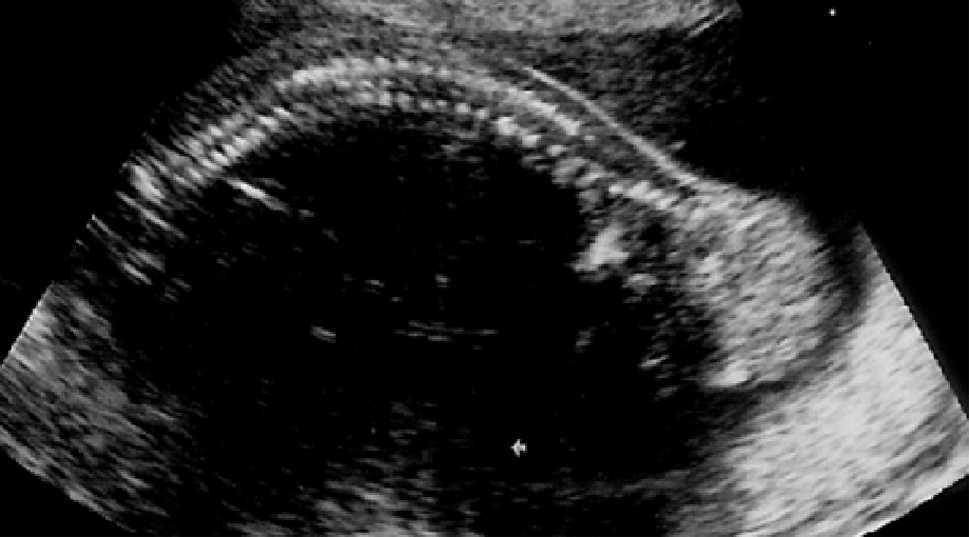

En la siguiente exploración ecográfica, en la semana 25 + 3, se observó un crecimiento de la tumoración con diámetros de 91 × 97 × 91 mm (fig. 3). No se observaban signos de sobrecarga cardíaca, y el Doppler del ductus venoso y la arteria cerebral media eran normales. Como hallazgo adicional a la ecografía anterior, se constató una pielectasia bilateral de 9 mm y un hidramnios (ILA 28) (fig. 4).

Figura 4. Ecografía realizada en la semana 25, donde se aprecia una pielectasia bilateral de unos 9 mm.